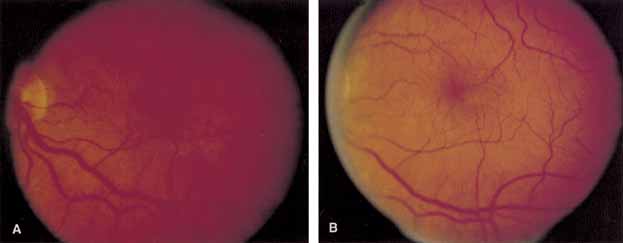

Optical coherence tomography or OCT is a relatively new tool used to diagnose macular lesions. It provides a unique view of the vitreoretinal architecture. OCT is particularly useful in diagnosing lamellar holes. With improvements in resolution and more widespread use, OCT will lead to new advances in the diagnosis and pathogenesis of macular holes (Fig. 2).